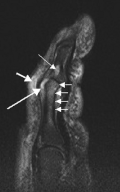

T2-weighted MRI (sagittal) of index finger in PsA (mutilans form) showing probable erosion (increased signal) at base of the middle phalanx (long thin arrow), synovitis at the proximal interphalangeal joint (long thick arrow), soft tissue edema (short thick arrow), and diffuse bone edema (short thin arrows) of the proximal phalanx. -